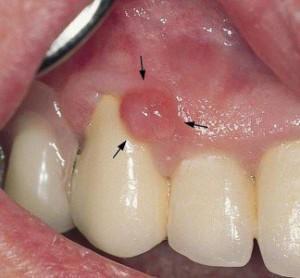

Новообразование внешне представляет собой вышедший за пределы десневого края участок. Вначале возникает воспаление десен, затем воспалительный процесс приводит к уплотнению и увеличению размеров участка десневой ткани. Иногда эпулис выглядит, как небольшая опухоль или бородавка красного и розового оттенка (см. также: ). Всего существует несколько видов десневых наростов, которые классифицируют следующим образом:

Ангиоматозный. Шероховатый нарост красного цвета, который часто кровит при надавливании. Новообразование быстро разрастается, велика вероятность рецидива после удаления.

- Гигантоклеточный. Новообразование с неровной бугристой поверхностью сильно контрастирует со здоровыми слизистыми (смотрите на фото). Эпулис обычно ярко-красного цвета или имеет синюшный оттенок. Любая травма может спровоцировать сильное кровотечение. Часто подобные образования перерождаются в раковую опухоль. С подобной патологией чаще сталкиваются люди в возрасте 40–60 лет.